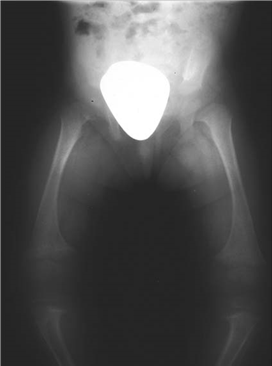

The radiograph above was performed on a child who presented with bowed legs.

What do you think the diagnosis is?

This plain radiograph of the pelvis and knees shows generalized widening of the metaphysis and cupping of the epiphysis in keeping with a metabolic condition such as rickets. Diff erential diagnosis would include a generalized skeletal dysplasia.

What is rickets?

Rickets is a disease of growing bone that is unique to children and adolescents. It is caused by a failure of osteoid to calcify in a growing person. Failure of osteoid to calcify in adults is called osteomalacia.

What are the causes of rickets?

z Nutritional rickets. (There are few dietary sources of vitamin D. The best ones are fatty fish such as salmon and sardines, and margarines supplemented with vitamin D. Milk contains added vitamin D in the USA but not in the UK. Most people in the UK get most of their vitamin D from exposure of the skin to sunlight)

z Lack of sunlight zCongenital rickets z Rickets of prematurity z Vitamin D resistance (type I and type II) z Neoplastic rickets z Hypophosphataemic rickets zDrug-induced rickets

How else might a child with rickets present, and how would you investigate them?

T he child may present with generalized muscular hypotonia of an unknown mechanism. In the long bones, laying down of uncalcifi ed osteoid at the metaphyses leads to spreading of those areas, producing knobby deformity which is visualized on radiography as cupping and fl aring of the metaphyses. Weight bearing produces deformities such as bowlegs and knock-knees. In the chest, knobbly deformities results in the rachitic rosary along the costochondral junctions. The weakened ribs pulled by muscles also produce fl aring over the diaphragm, which is known as the Harrison groove. The sternum may be pulled into a pigeon-breast deformity. At the ankle, palpation of the tibial malleolus gives the impression of a double epiphysis (Marfan sign).